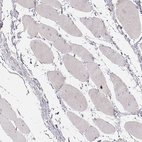

Immunohistochemistry analysis in human bone marrow and skeletal muscle tissues using HPA041564 antibody. Corresponding ABCA7 RNA-seq data are presented for the same tissues.